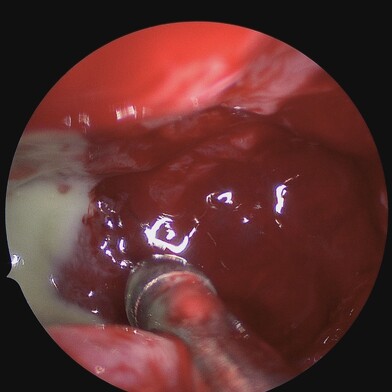

Diagnosing chronic rhinosinusitis involves a comprehensive evaluation, which may include medical history and physical examination, nasal endoscopy, imaging studies, allergy testing, and conducting nasal and sinus cultures.

Treatment can be initiated with regular medications like nasal steroid sprays, anti-histamine tablet and sprays, antibiotics, nasal saline sprays, or oral corticosteroids. But specific problems causing rhinosinusitis may be treated with Functional Endoscopic Sinus Surgery (FESS).